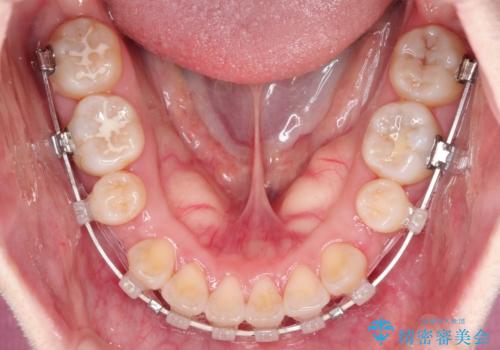

- 矯正装置

- 審美装置

- 治療期間

- 1年10ヶ月

- ”口元を下げたい”が主訴で来院されました。

抜歯してワイヤー矯正を行い、口元も改善され大変満足していただきました。

小臼歯の抜歯を行うことで口元を改善することができました。